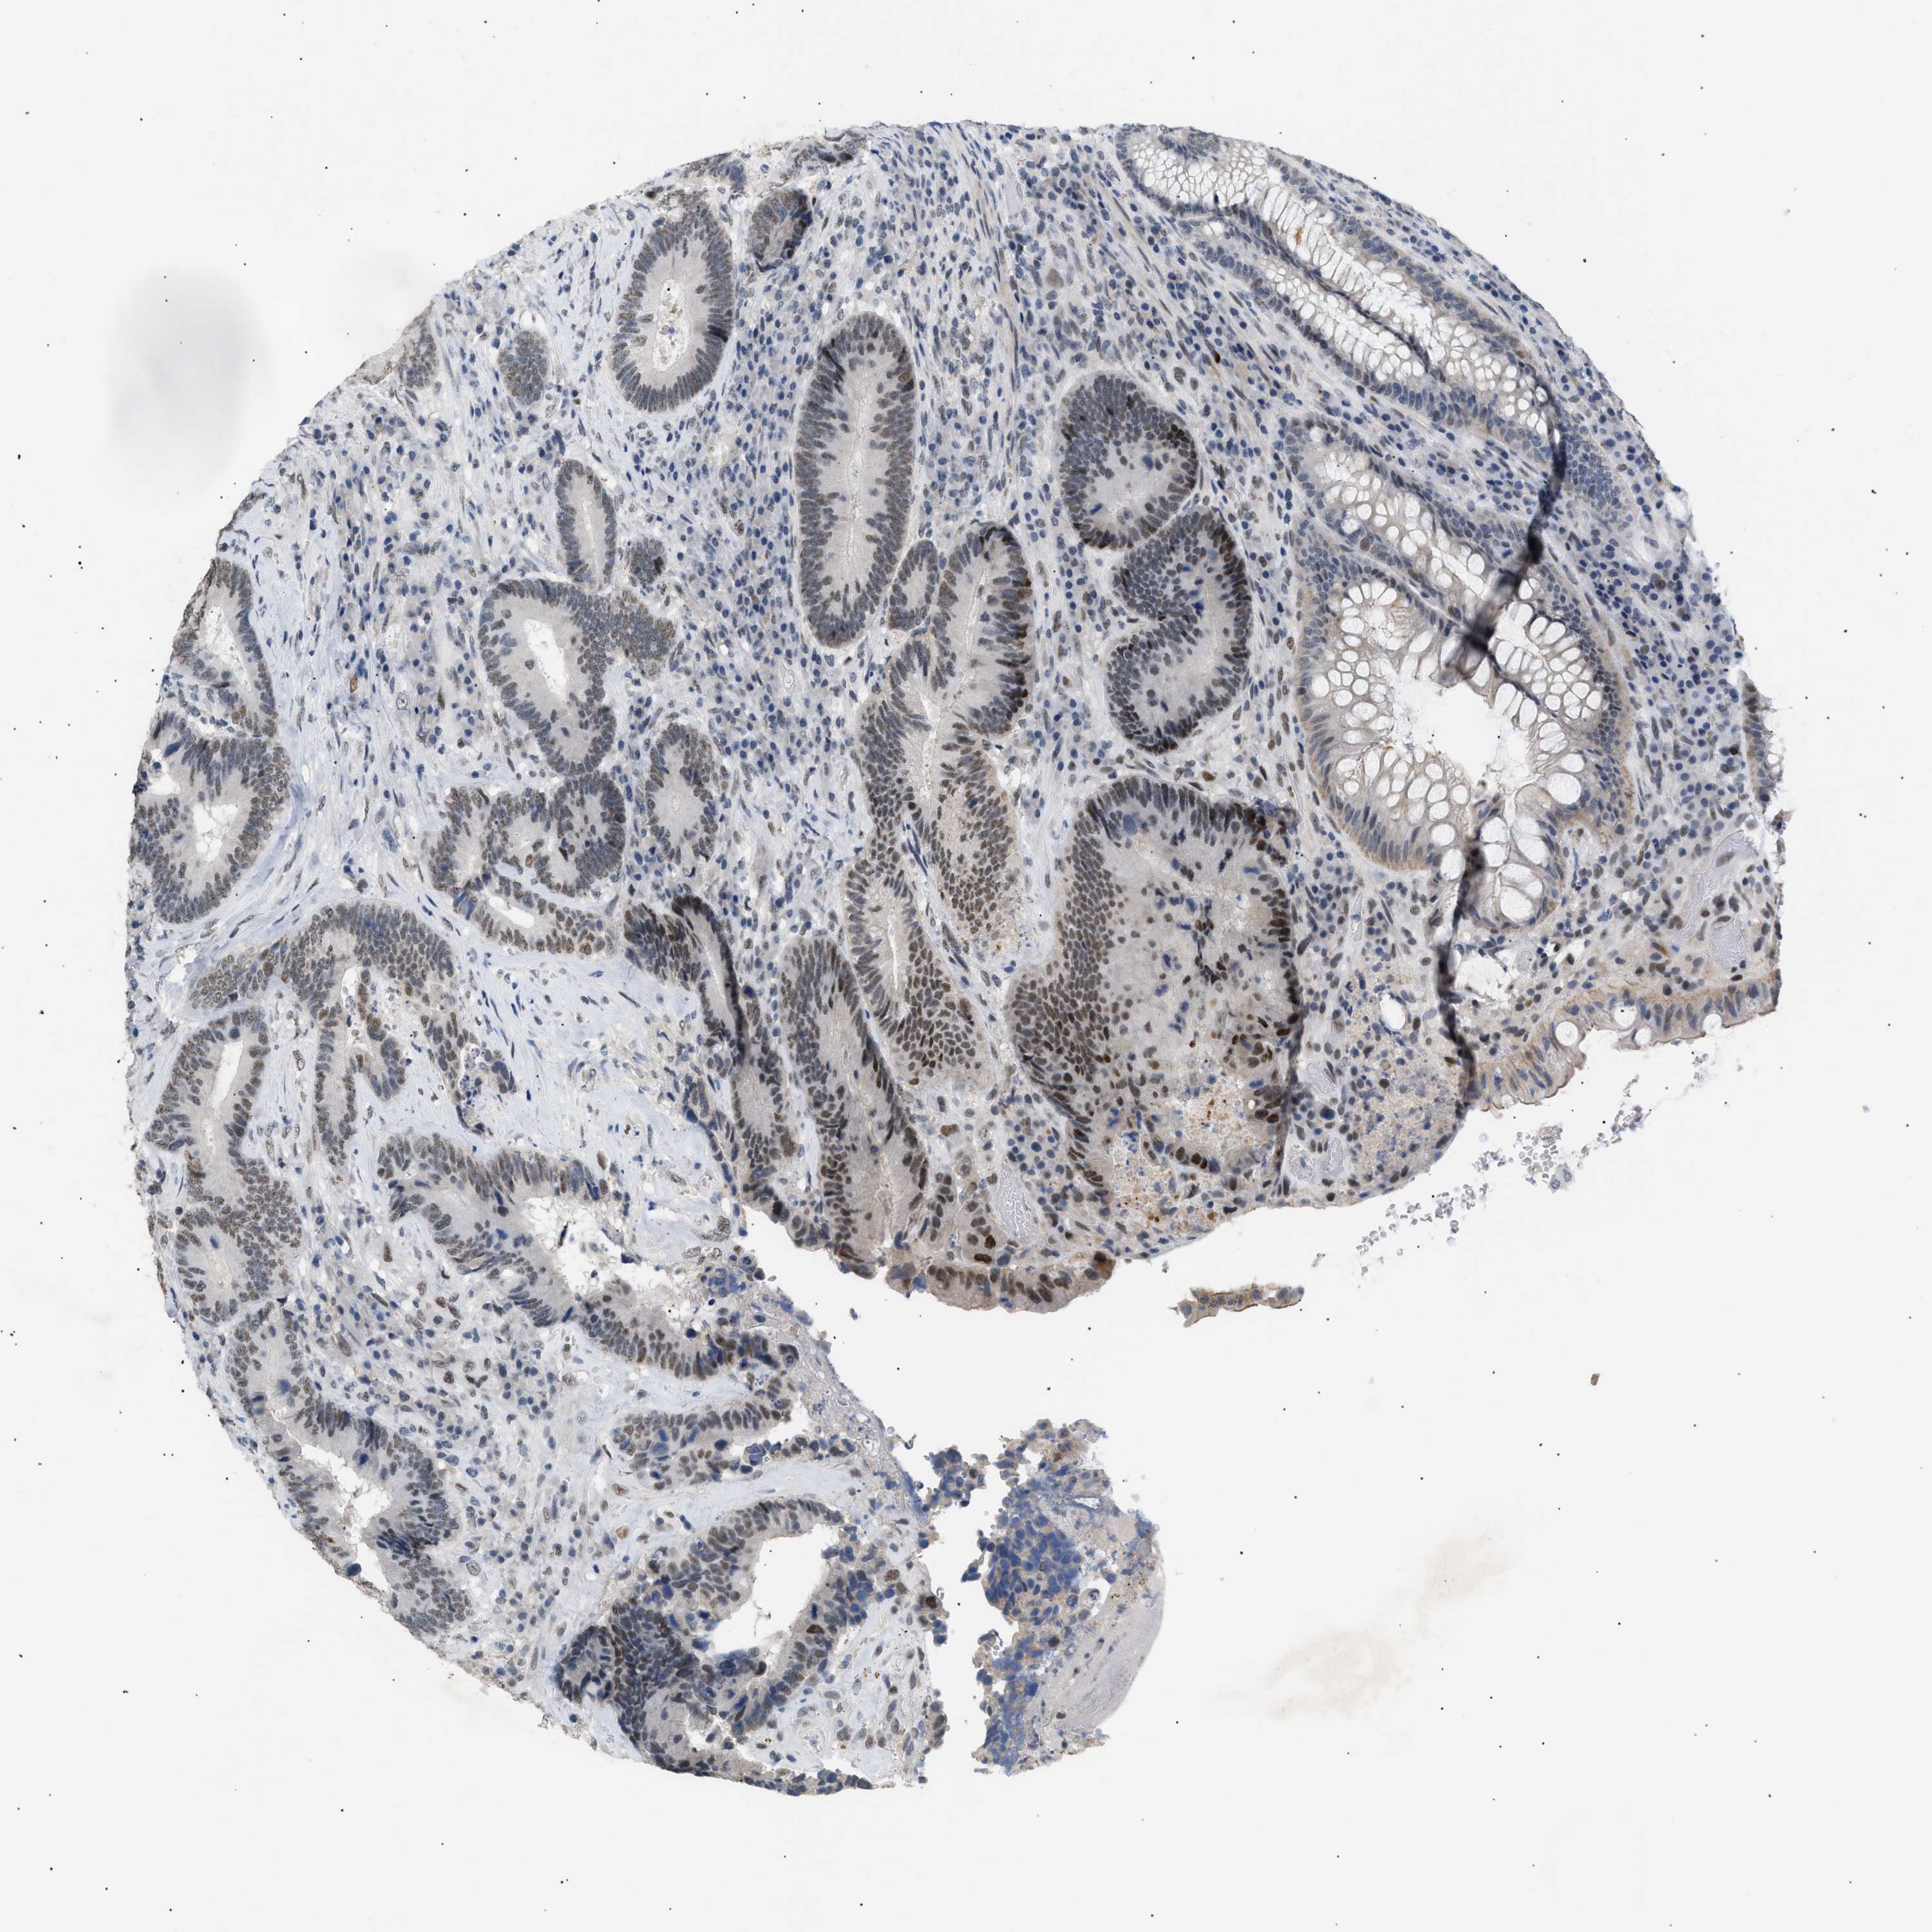

CANCER COLORECTAL CANCER Show tissue menu

Colorectal cancer

Human cancer

Colon adenocarcinoma